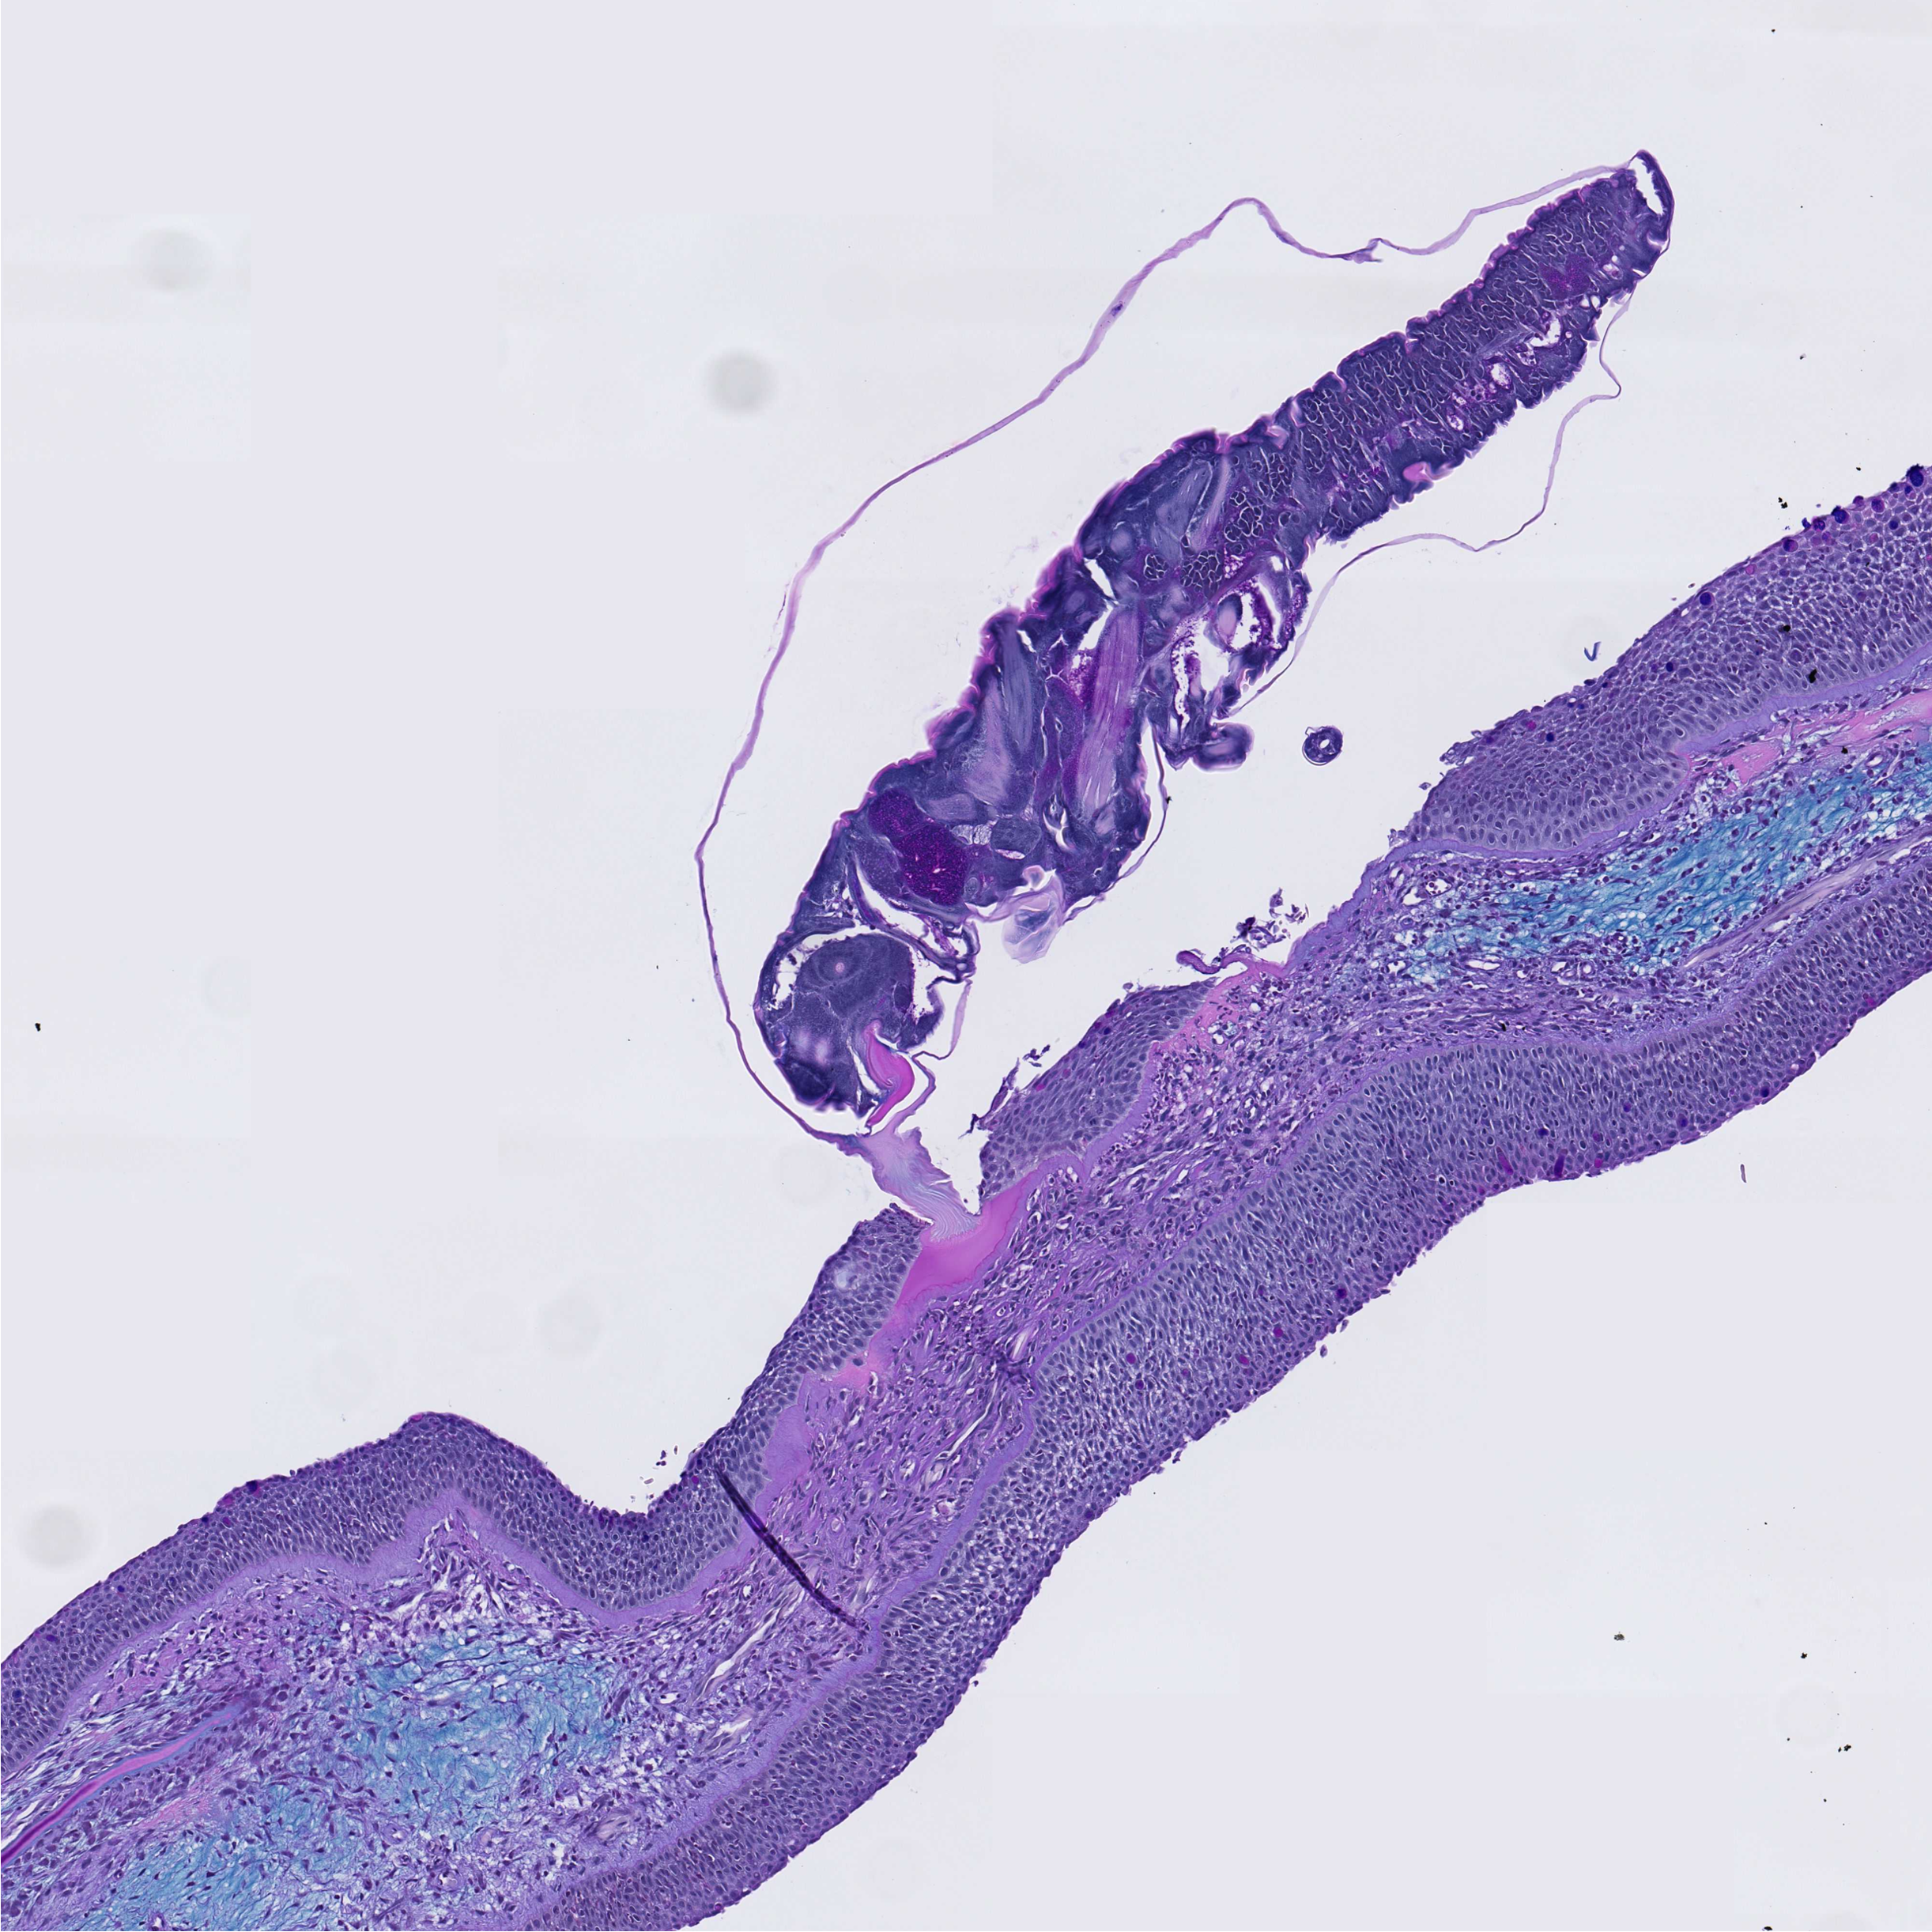

Forskerne fant at sølvlaks setter i gang en kraftig betennelsesreaksjon innen to døgn etter at lusen har festet seg. Immunceller strømmer til området og gjør det vanskelig for parasitten å etablere seg. Til sammenligning reagerer Atlantisk laks langt svakere.

Ikke bare sølvlaks, men også andre stillehavsarter som hundelaks (chum salmon) og pukkellaks (pink salmon), viser imponerende forsvar mot lakselus. Studien viser at de har høy tetthet av slimceller i huden. Når disse artene ble smittet med lus i forsøket, måtte laksen bedøves for at lakselus skulle klare å feste seg.

− Det tyder på at hudoverflaten deres i utgangspunktet er lite egnet for parasitten, og at det er flere mekanismer som virker inn, forklarer Sveen.

- Det unike ved akkurat dette studiet i CrispResist: Ved å zoome inn på det første kontaktpunktet mellom lus og vert, har forskerne kunnet avdekke tidlige og svært lokale immunreaksjoner som ellers ville blitt "utvannet" i helkroppsanalyser.